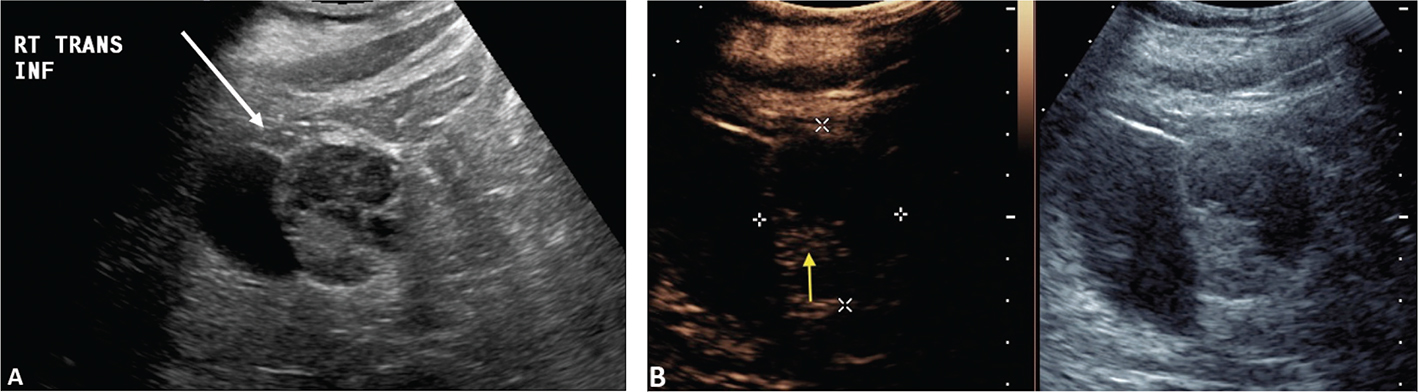

CEUS can be used to follow patients for residual or recurrent tumor with high accuracy. Any residual tumor will be identified as areas of increased enhancement. Absence of blood flow as in Figure 3B confirms complete ablation of the renal tumor. Note that it is not possible to determine if contrast is not utilized in Figure 3A. Figure 4 demonstrates a case where residual tumor (calipers) is present.

Figure 3. Successful ablation. Patient presented for 3-month post-RFA evaluation. (A) B-mode image before the ablation. Large heterogeneous tumor is noted on gray scale examination (arrow). (B) Absence of residual blood flow (arrow) is demonstrated on CEUS examination.

Figure 4. Tumor recurrence/inadequate ablation. Patient presented for CEUS examination 6 weeks after RFA. (A) The B-mode image demonstrates a complex mass (arrow) with solid and cystic components. It is not possible to determine if there is residual tumor. (B) CEUS image demonstrates the tumor (calipers) with residual flow in the posterior part of the tumor (arrow).